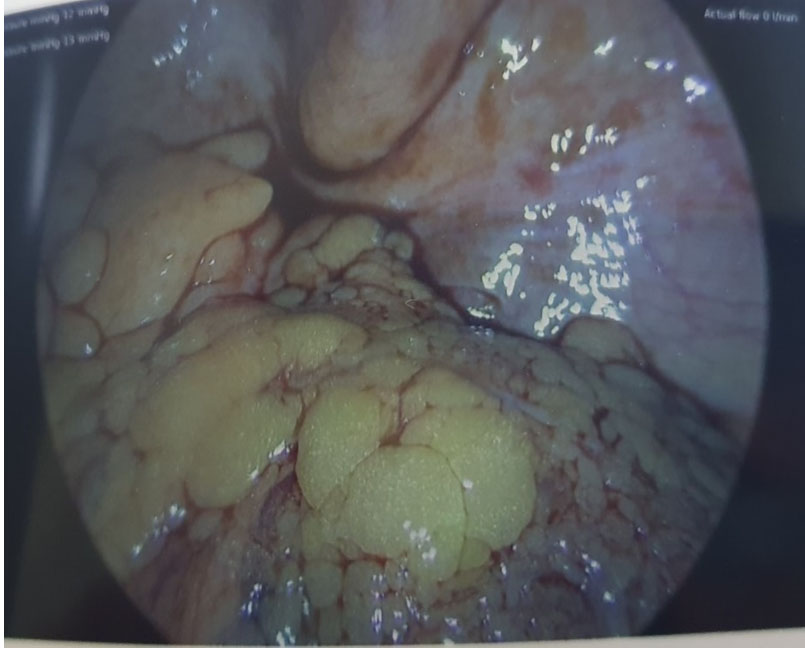

She had a laparoscopy appendectomy the next day. The appendix and mesoappendix appeared thickened with extensive endometriosis in pelvis and left ovary endometrioma were visualized (Figure 4 and Figure 5). The appendix was removed and she was discharged home the next day. Her histology result showed two foci of endometrial present in the subserosa of the appendix with surrounding endometrial stroma and no atypical features seen. There was also mucosal lymphoid hyperplasia but no transmural neutrophilic infiltrate which indicated no acute inflammation of the appendix.

Figure 5: Endometriosis of the left ovary.